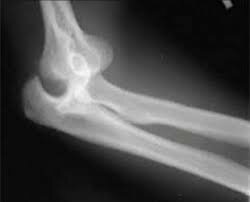

• Curación de fractura con el uso de  Rx

Curación de fractura con el uso de Rx

1914-1918: M. Curie cura de fracturas mediante RX y uso de RX móvil en la guerra mundial.